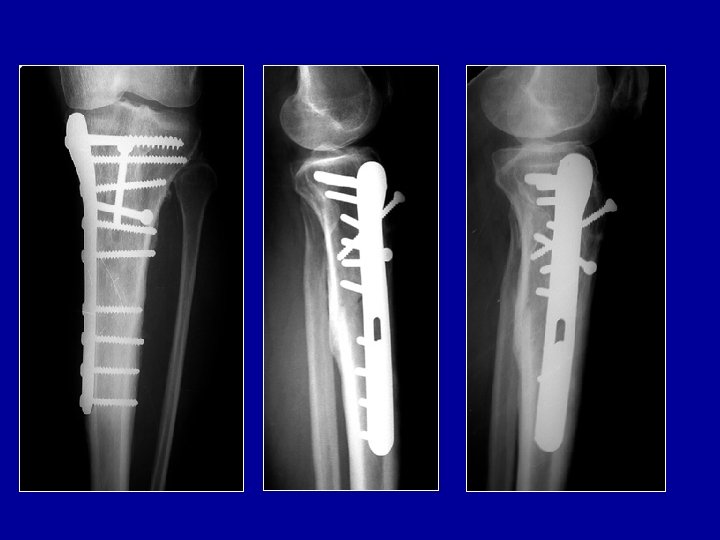

Clou de tibia Verrouillage proximal Verrouillage distal Photo J. Chouteau

Clou à foyer fermé verrouillé Vis enlevées à 3 mois Guérison 6 mois

Ostéosynthèse du tibia par plaque vissée Plaque sur la corticale externe ou interne

Exemple d’ostéosynthèse mixte : clou verrouillé pour le tibia et plaque pour le péroné

Traitement de plusieurs fractures associées Fracture du tibia : clou centro-médullaire Fracture du péroné : plaque Fracture de la malléole interne : 2 vis Photo J. Chouteau